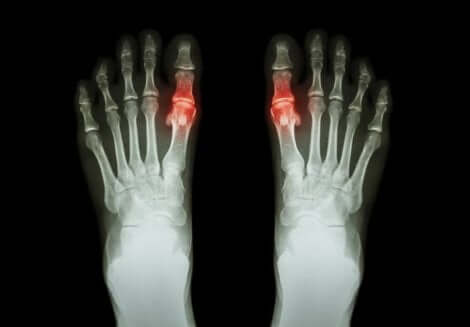

Artriitti ilmenee yleensä kipuna ja vaikeuksina liikuttaa tulehtunutta niveltä/niveliä. Toisinaan siihen liittyy myös alueen jäykkyyttä ja turvotusta. Artriitti voi vaikuttaa vain yhteen niveleen tai useisiin niveliin yhtä aikaa. Se voi lisäksi olla symmetristä tai epäsymmetristä.

Jokaisella muodolla on omat erityispiirteensä, ja oireiden kesto vaihtelee. Esimerkiksi nivelreuma on artriitin symmetrinen muoto, joka vaikuttaa pieniin niveliin, kuten sormiin. Kihti puolestaan on sellainen artriitin muoto, joka vaikuttaa yleensä vain yhteen niveleen.